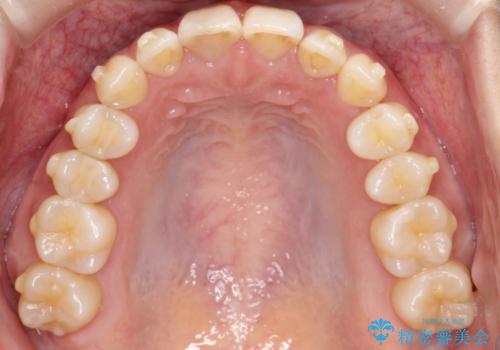

ディープバイト改善のためのインビザライン治療

- 患者様は、全体的な歯列のガタガタとディープバイト(深い噛み合わせ)を主訴として来院されました。診断の結果、ディープバイトを改善するためには、歯列全体の拡大が必要であると判断しました。治療には、透明なマウスピース型矯正装置「インビザライン」を使用し、歯を適切に拡大しながら歯並びを整える計画を立てました。治療期間はおおよそ2年を見込んで進め、最終的に見た目にも大きく変化をもたらすことを目指しました。

ディープバイトの治療には、奥歯の高さや前歯の位置に対する繊細な調整が必要です。本症例では、インビザラインによる歯列拡大を行うことで、噛み合わせを改善し、歯並び全体を整えました。治療過程では、歯間のスペースを確保するため、IPR(インタープロキシマルリダクション)を適宜行い、無理なく歯列の調整を行いました。治療後は、歯並びが大きく改善され、患者様の見た目にも大きな変化が現れました。インビザラインは透明で目立たず、治療中の見た目を気にされる患者様にも配慮した治療法です。